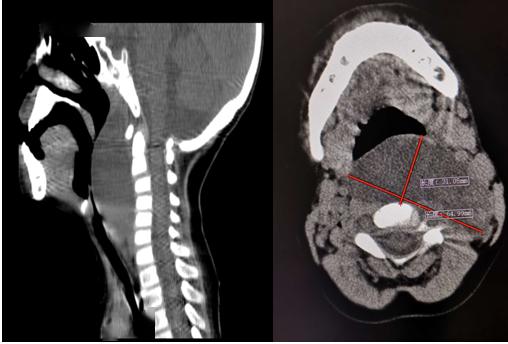

头皮鳞状细胞癌面部皮肤癌⑥咽旁间隙肿物,头皮-颜面-颈部皮肤肿瘤;眼